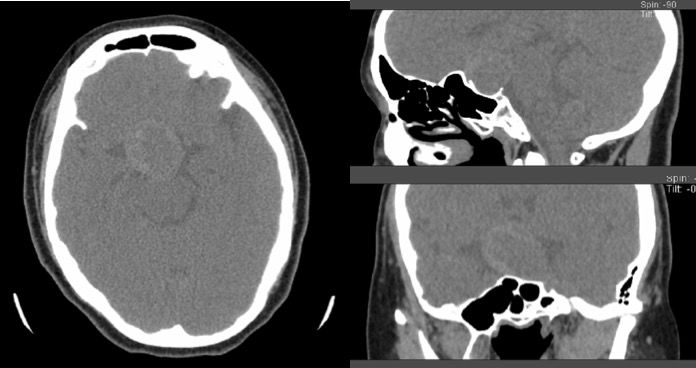

鞍区CT:鞍区内见软组织团块灶,平扫中间稍低密度,周边呈稍高密度,未见钙化灶,邻近骨质受压吸收(图3)。

图3. CT检查显示鞍区病变,未见钙化。